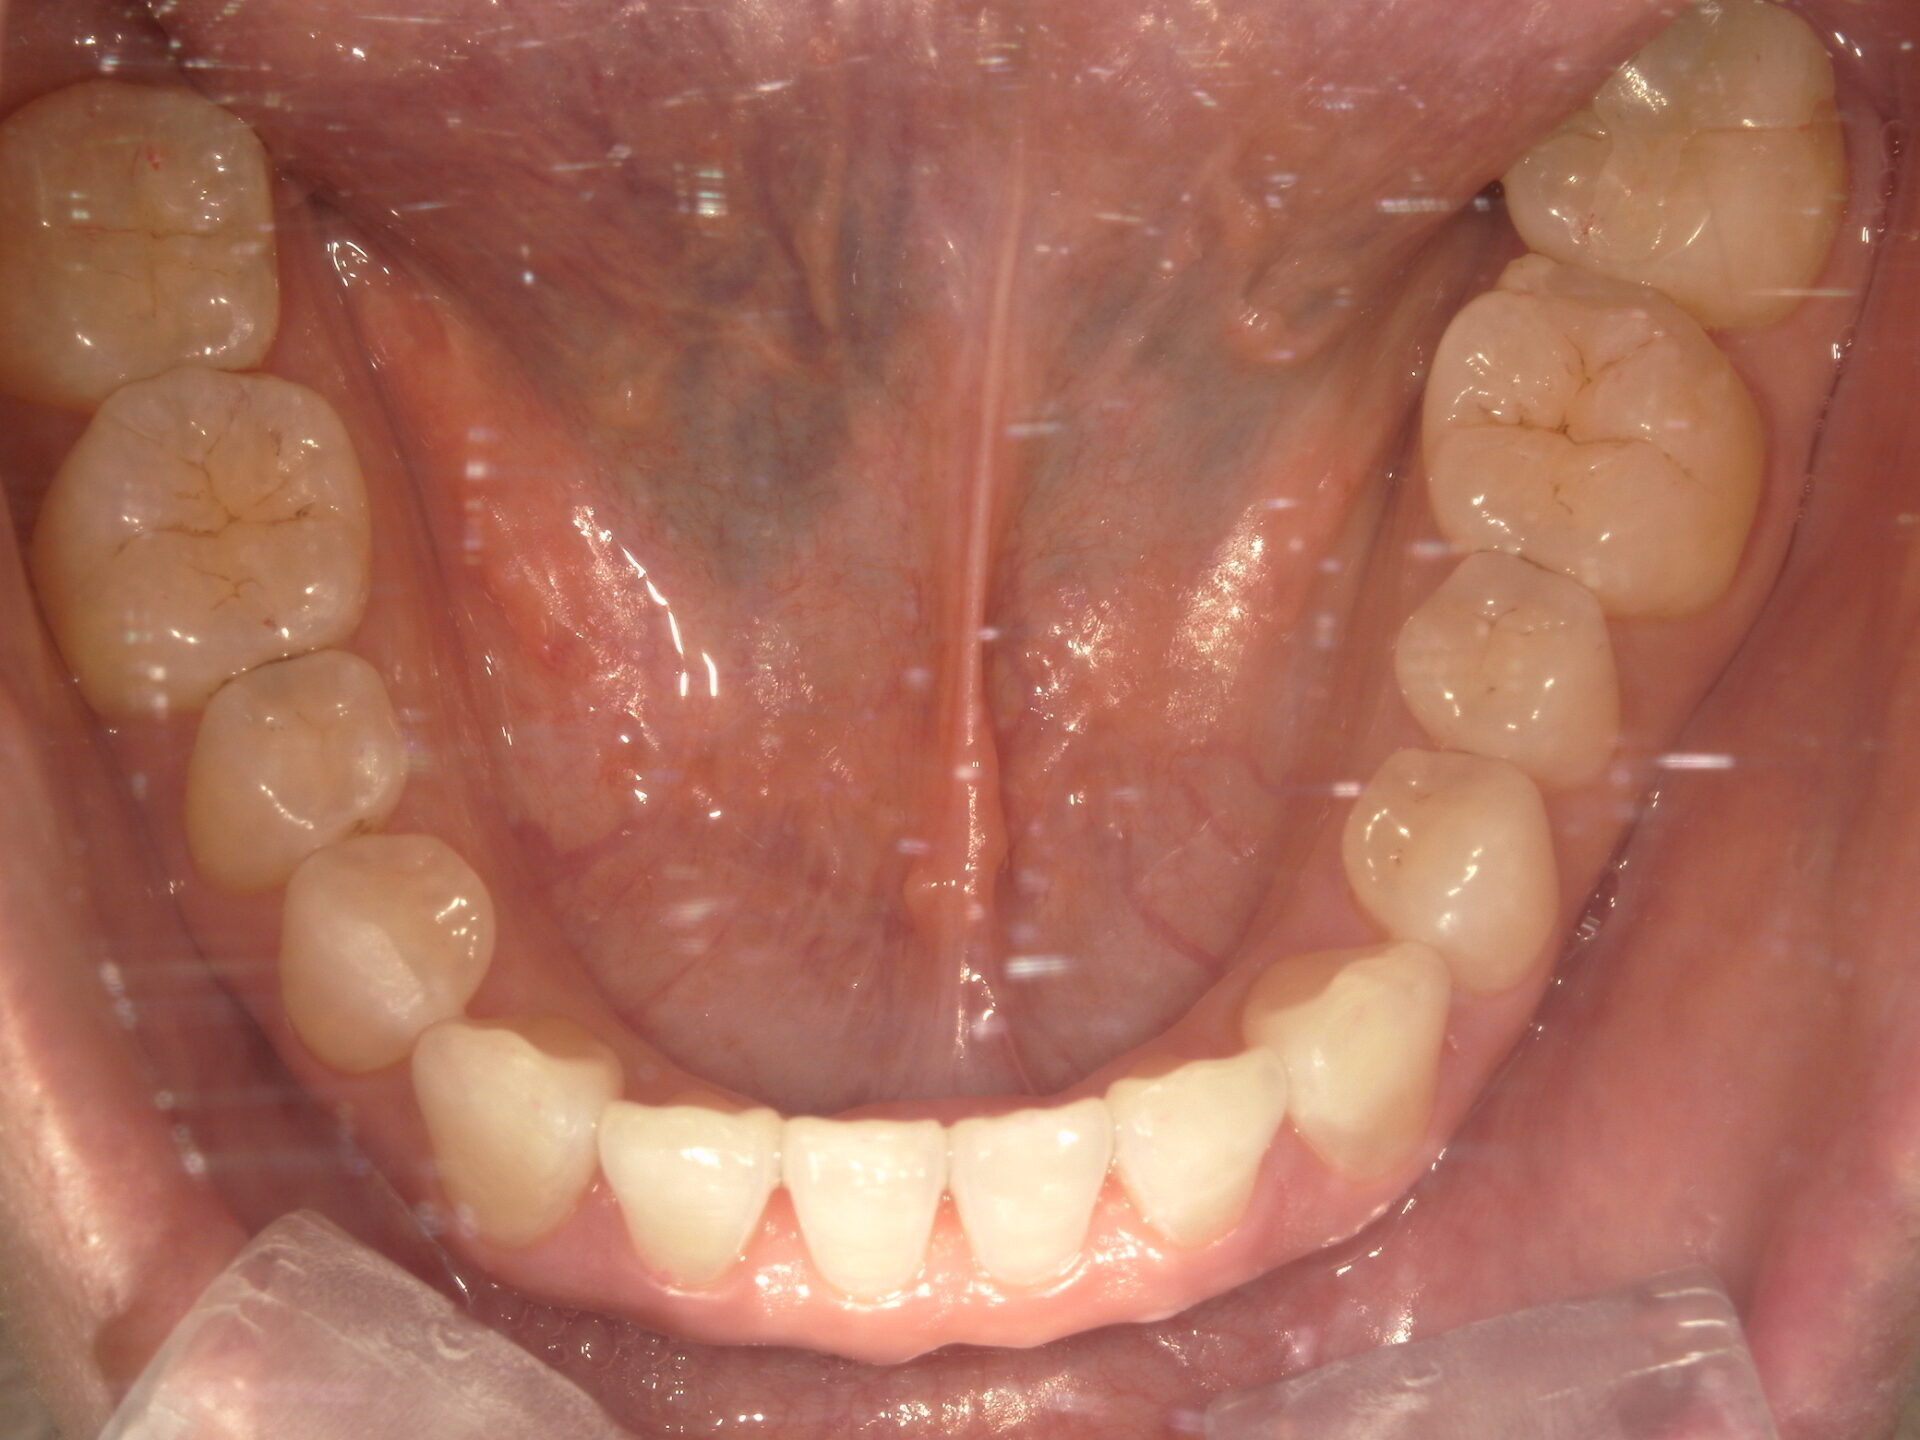

before

患者さんの年齢 20代 女性 症状 見た目が良くなりたい 治療内容 マウスピース矯正治療 費用 90万(税抜) 治療期間・回数 治療期間2年半、通院回数20回 メリット スマイルラインが綺麗 デメリット・リスク 期間がかかることがある 患者さまの声 見た目が綺麗になった - マウスピース矯正